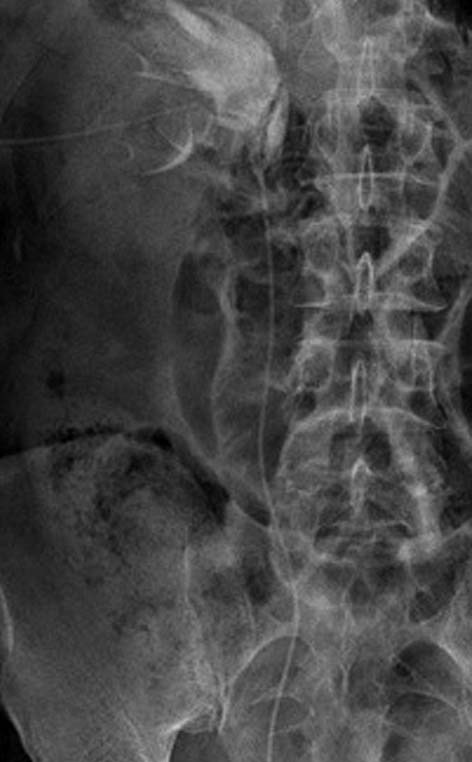

При ультразвуковом исследовании определено скопление жидкости в правом периренальном пространстве, выявлена гидронефротическая деформация правой почки. Левая почка обычных размеров с единичными простыми кистами. Для уточнения диагноза было проведено рентгенологическое обследование, по результатам которого диагностированы МКБ, конкремент правого мочеточника в верхней трети, дефект стенки лоханки правой почки в области пиелоуретерального сегмента с затеком контрастированной мочи в паранефральную, парауретеральную и забрюшинную клетчатку (рис. 1 а, б).

Рис. 1. Компьютерная томография:

а — конкремент верхней трети правого мочеточника, уринома справа; б — разрыв ЧЛС правой почки, уринома справа.

Рис. 2. Рентгенограмма. Дренированная правая почка